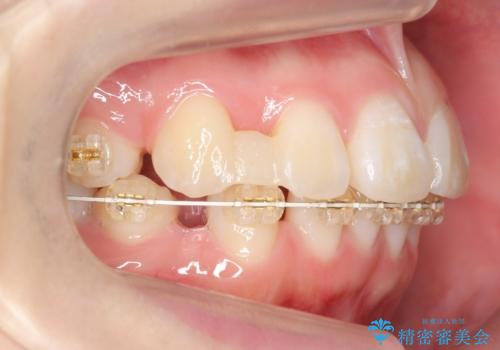

成人式に間に合う 前歯の矯正

- 前歯のがたがたを主訴に来院。

口元も下げたいとのことでした。

成人式の1年前から矯正をはじめ、成人式前に上の前歯の装置を一時的にとりました。

一時的に装置を取ることで、多少治療期間が伸びましたが、それでも、2年かからずに外すことができました。

成人式の時に前歯が下がって、揃った状態で写真を撮ることができ、大変喜んでおられました。